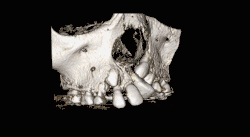

![]() CBCT scan of the maxilla in an 11 year old showing a left alveolar cleft. | |

In cases with a single cleft, 35-60% of lateral incisors are congenitally missing,[4] and cannot be relied on for timing. Instead, the eruption of the incisors and first molars is used as a queue to begin assessments. With bilateral cases, the premaxilla must be repositioned before grafting and special consideration must be given. During this time, the orthodontist must be wary of rotating teeth into the cleft site. Last, the size of the patient, defect, and social issues must all be taken into consideration and is best assessed with a CBCT scan as the patient enters the mixed dentition phase of dental development.[5]